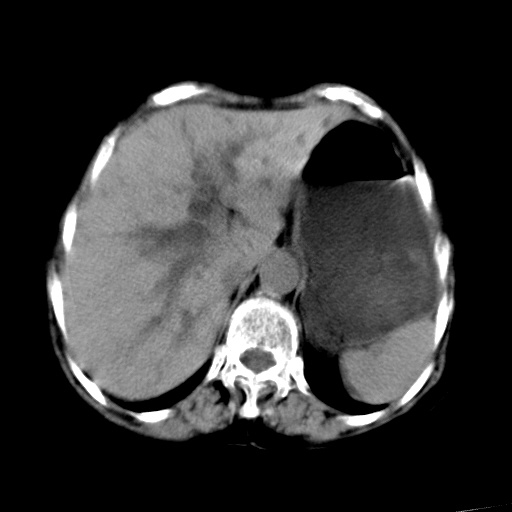

以下是引用杀毒软件在2009-3-4 17:38:00的发言:[br]为何没有喝照影剂呀? 胆总管及肝内胆管扩张,增强吧。[br][br]考虑-----十二指肠占位----建议----十二指肠镜检查[br][br]

以下是引用jiangjing在2009-3-4 17:45:00的发言:[br]低位胆道梗阻。十二指肠降段局部管壁增厚。扫描效果不理想,建议ct增强及ercp。

以下是引用杀毒软件在2009-3-4 17:38:00的发言:[br]为何没有喝照影剂呀? 胆总管及肝内胆管扩张,。增强吧。[br][br]考虑-----十二指肠占位----建议----十二指肠镜检查[br][br][br][br][本贴已被 杀毒软件 于 2009-3-4 17:56:38 修改过]